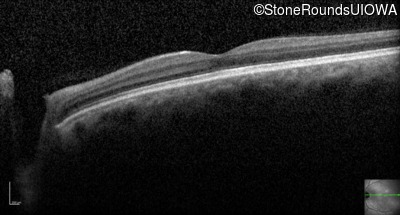

Optical Coherence Tomography - Right - 20/200

Exemplar / OCT Stack

OCT Stack